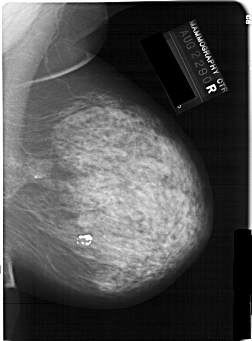

A_1146_1.RIGHT_MLO

RIGHT_CC LINES 6646 PIXELS_PER_LINE 4576 BITS_PER_PIXEL 12 RESOLUTION 43.5 NON_OVERLAY

RIGHT_MLO LINES 6466 PIXELS_PER_LINE 4771 BITS_PER_PIXEL 12 RESOLUTION 43.5 NON_OVERLAY